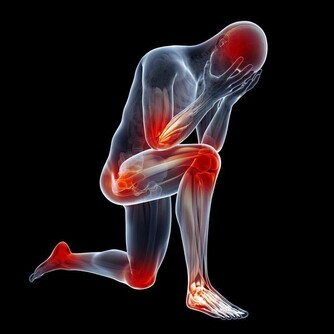

***(二)腿腳莫名的疼痛***

如果腿部血管出現硬化,那麼最明顯的表現就是莫名疼痛。可能一些輕微的血管硬化,在我們行走時會出現痛感,如果稍作休息就會有所緩解,但是一些程度比較嚴重的血管硬化,它的痛感非常明顯,如果放任不管,最終就會形成間歇性跛行。

***(三)腿腳腫脹發麻***

血管有硬化的趨勢時,人體的血液流動速度就會受到影響而變得緩慢,不​​加以控制就會導致腿部得不到足夠的氧氣以及養分,所以才會出現腫脹發麻。當然這种血管堵塞,一般情況下會出現單側堵塞。